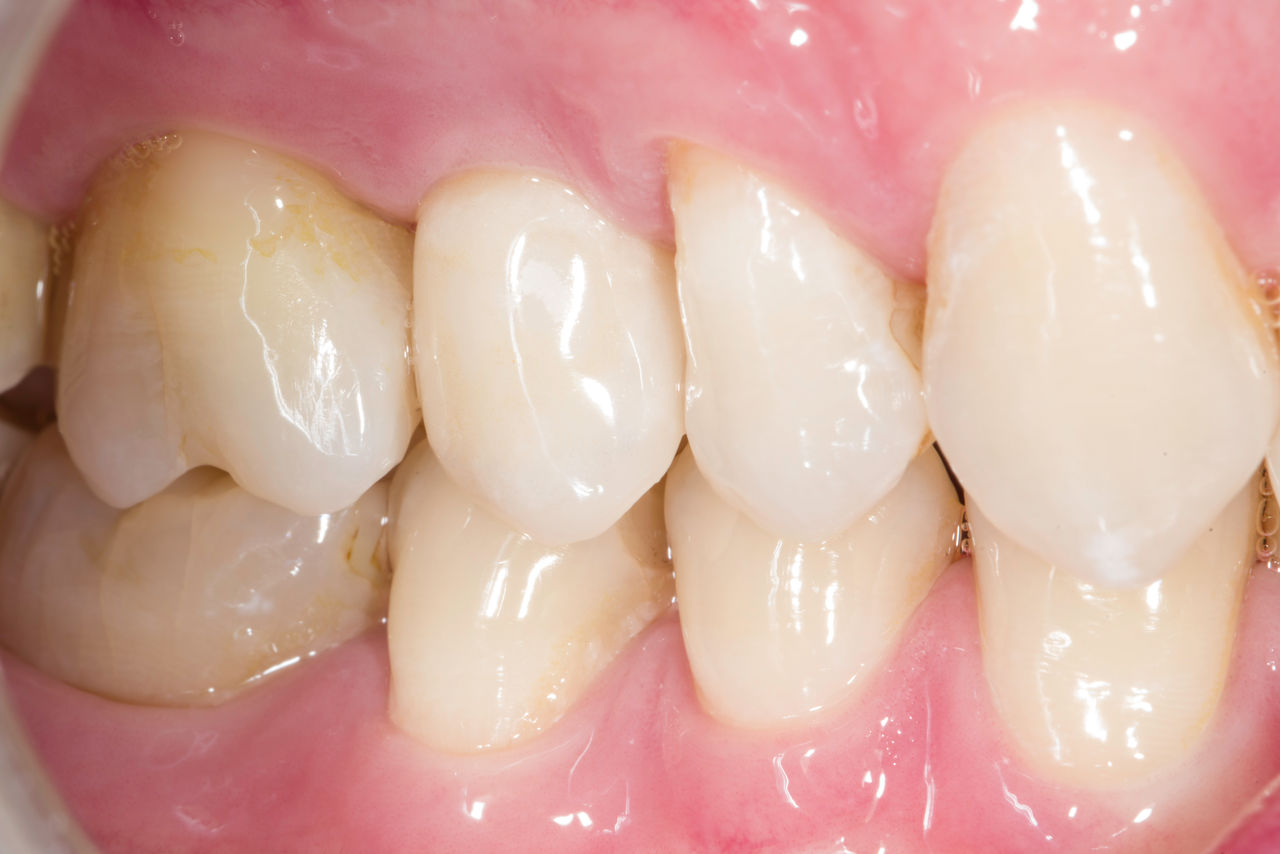

Before

Fractured ceramic restoration made from a leucite-reinforced glass-ceramic after a clinical service time of 12 years.

After

Chairside-fabricated restoration made from an advanced lithium-disilicate ceramic CEREC Tessera.